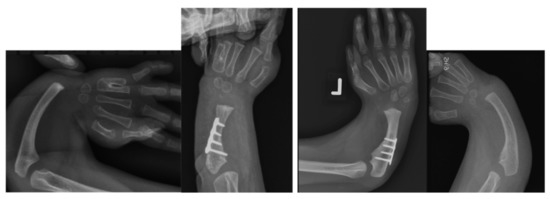

Figure 4.

Case 9 left, 10 right. Bilateral RCH preop radiographs (left most, right most). Postop radiographs after ulnarization G3 of both hands (left middle, right middle). Note the hypertrophy of the head of the ulna after surgery in both hands.